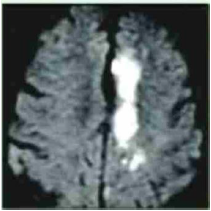

Analise a imagem abaixo, que apresenta uma ressonância.

Essa ressonância é característica de:

Fonte: Banca examinadora.